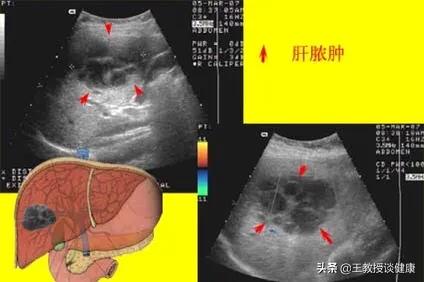

彩超检查显示的肝右叶肝脓肿影像